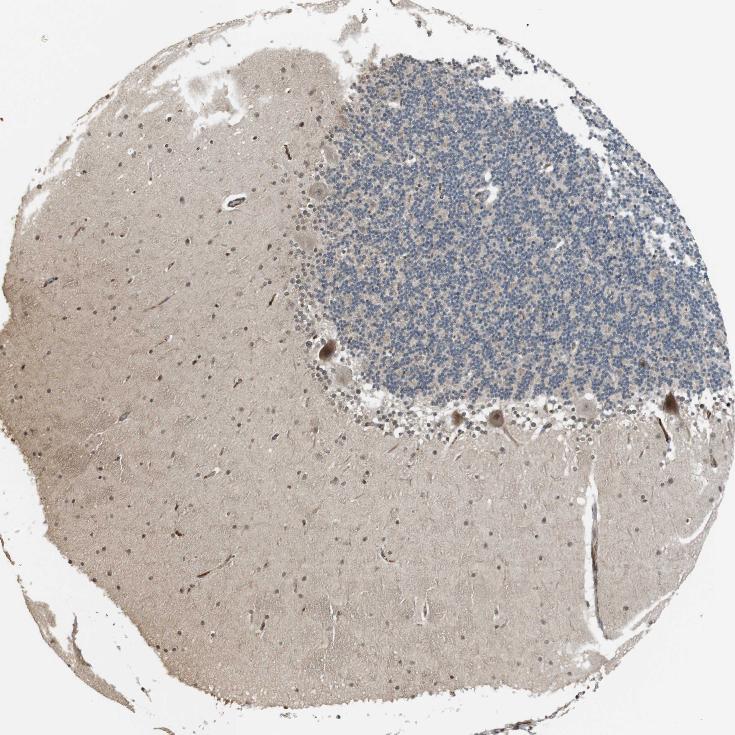

BRAIN CEREBELLUM Show tissue menu

CEREBELLUM - Antibody stainingi

Antibody staining in the annotated cell types in the current human tissue is reported as not detected, low, medium, or high, based on conventional immunohistochemistry profiling in selected tissues. This score is based on the combination of the staining intensity and fraction of stained cells.

Each image is clickable and will lead to virtual microscopy that enables deeper exploration of all samples and also displays staining intensity scores, fraction scores and subcellular localization as well as patient and tissue information for each sample.

Antibody CAB015343

Purkinje cells Medium

Cells in granular layer Not detected

Cells in molecular layer Low